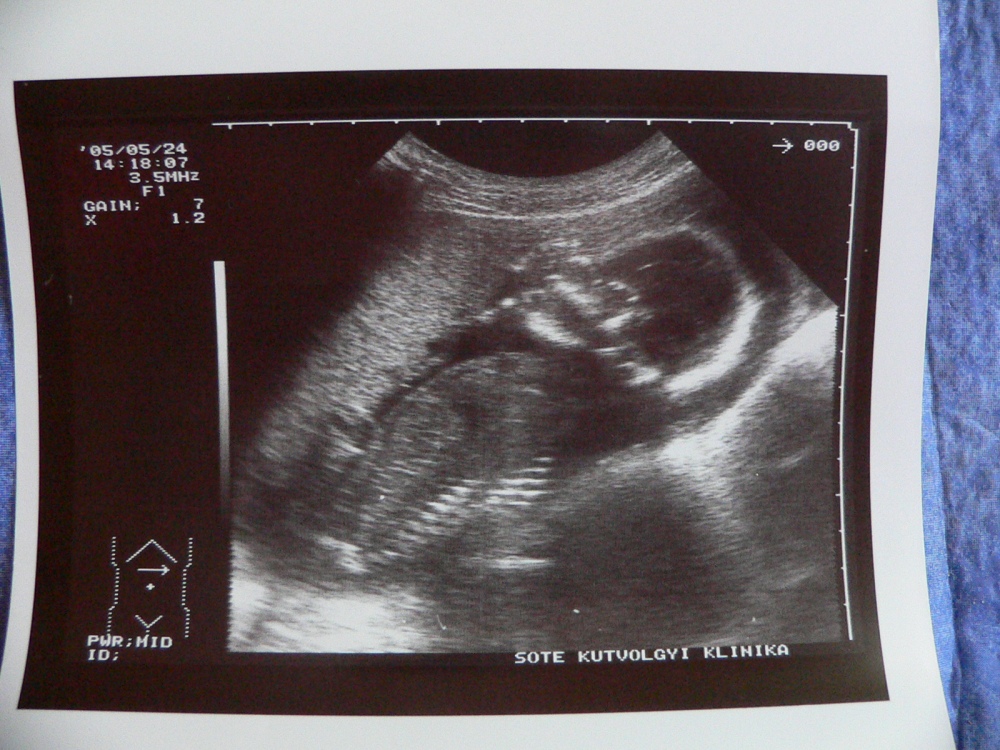

| 5 hetes, 4.5 mm. A kis nyilacska szerűség mutatja a szívét. Mellette a függőleges vonalak a szívverését mutatják.. :-) | |